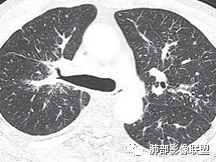

三、影像表现:左肺上叶多发片状高密度影,散在,边缘模糊,支气管壁稍增厚,中轴间质、小叶间隔增厚、有结节感,左肺上叶前段病灶可见胸膜增厚,部分小支气管不能分辨;右肺上叶后段混合磨玻璃结节,边界清,邻近胸膜凹陷;纵膈淋巴结肿大;心包增厚;左侧少量胸水。此外,扫及右侧胸腔内甲状腺肿;左侧肩胛骨旁肌群内脂肪瘤。

四、综合分析:老年男性,以咳嗽咳痰为主要临床表现,无发热,白细胞正常,影像表现为左肺上叶片影,前段结节影、胸膜增厚、部分小支气管不能分辨。左肺上叶中轴间质增厚、小叶间隔增厚、结节感,肺门纵隔见肿大淋巴结,尽管肺部病病灶边缘特征不典型,但高度疑及癌性淋巴管炎这一“次生灾害”却具有相当重要提示意义,而肺癌中最常伴癌淋的就包括腺癌。右肺上叶后段混合磨玻璃结节,边界清楚,张力明显,具有一定特征性,高度指向浸润性腺癌。这对于左肺病灶具有一定程度“助攻”效应。总体而言,本例左肺病灶的诊断关键点在于判断出癌性淋巴管炎。癌性淋巴管炎的结节在外围间质多见,小叶间隔可呈串珠状、结节状增厚,由于出血及水肿,小叶间隔增厚较明显,或呈不规则增厚。有的肺小叶呈多角状阵列。常合并胸水。